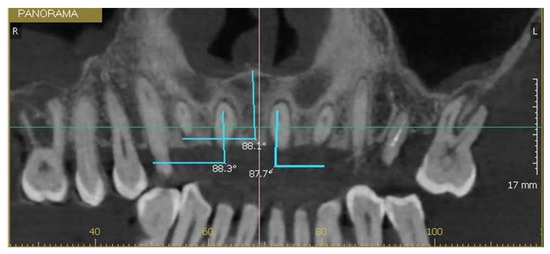

The longitudinal axis of each incisor was defined as the line connecting the incisal edge with the root apex, while the axis of the NPC was defined by marking a line between the nasopalatine foramen, superiorly, to the incisive foramen inferiorly. The MDI of 1.1 and 2.1 was calculated as the angle between their longitudinal axis and a transverse reference plane passing through the midline of the maxilla. The same measurement was applied to the NPC relative to this plane (Figure 3). The VPI of 1.1 and 2.1 was determined as the angle between their longitudinal axis and the horizontal plane, with the NPC measured in the same manner (Figure 4 and Figure 5).

Figure 3. Mesiodistal inclination of tooth 1.1, the canal, and tooth 2.1.